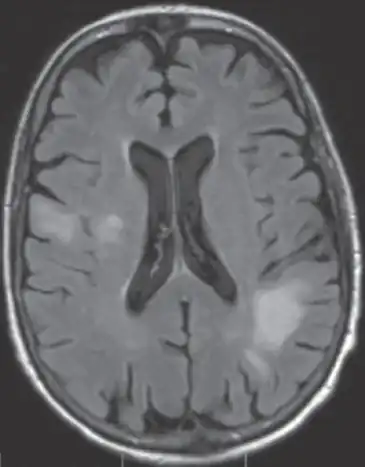

High signal intensity lesion of white matter of dorsal right frontal lobe/right frontal operculum

Characteristic evidence of PML on brain CT scan images are multifocal, noncontrast enhancing hypodense lesions without mass effect, but MRI is far more sensitive than CT.[17] The most common area of involvement is the cortical white matter of frontal and parieto occipital lobes, but lesions may occur anywhere in the brain, such as the basal ganglia, external capsule, and posterior cranial fossa structures such as the brain stem and cerebellum.[17] Although typically multifocal, natalizumab-associated PML is often monofocal, predominantly in the frontal lobe.[17]